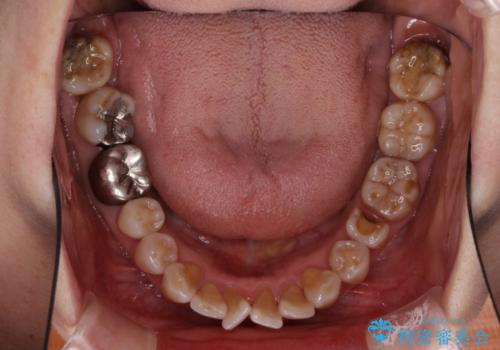

- 突出した口元を引っ込めることを希望して来院された患者様です。

上下左右第一小臼歯4本を抜歯して、口元を改善するワイヤー矯正を行うこととしました。

長年気にされていた口元の突出感が改善されたため、もっと若い時分に矯正をすればよかったと思われていました。